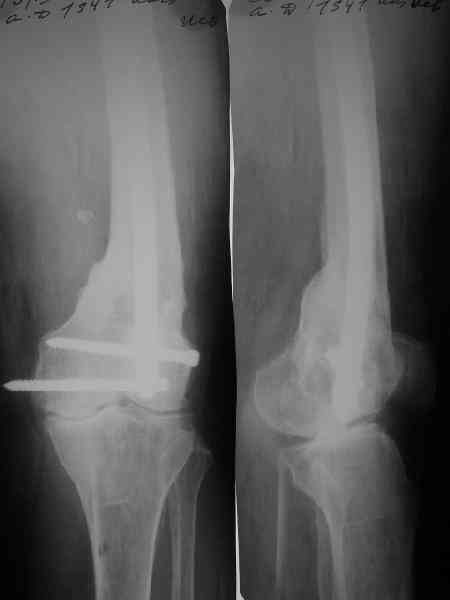

Доброго времени суток,уважаемые коллеги! Прошу вашего мнения. Больная, 53 лет,поступила с диагнозом: Ложный сустав н/3 бедренной кости слева. Травма в 1995г. Закрытый перелом н/3 левого бедра,лечение скелетным вытяжением. 15 лет ходила без трости. В 1-2010 года, рефрактура левого бедра в н/3. Лечение консервативное, скелетное вытяжение 2,5 месяца. Выписана в полужестком туторе. На ногу не опиралась, передвигается при помощи костылей. Инвалид 3 гр. посттромбофлебитический синдром левой нижней конечности. По дуплексному сканированию сосудов нижних конечностей вены проходимы, только на голени подкожная вена "посттромбофлебитическая".Из сопутствующих: ГБ,ДУЗ 0ст.Ожирение 1 ст.Предлагается костная пластика одним из существующих методов, накостный синтез мыщелковой пластиной LSP (Synthez). Укорочение левой ноги 3,5 см. Есть опасение, что накостный синтез ограничит периостальную регенерацию, да и травматичность операции при сопутствующих заболеваниях опасна в плане осложнений. Хотелось бы узнать мнение о ЧКДО и интрамедуллярном синтезе у данной пациентки. Стоит ли сначала "срастить" перелом, а потом коррегировать длину конечности? Или это нужно делать сразу? Может быть вообще ничего не делать и разрешить нагрузку? Пробую приложить Rn-гр. и томогр. Извиняюсь за качество обработки. Спасибо. Надеюсь на ваше понимание.

Смещение по длине см на 3 видно на снимке. Удобно и нетравматично восстановить длину и устранить смещение по ширине аппаратом.

По всей вероятности, после перелома бедренной кости, случившегося 15 лет назад, у больной сформировался псевдоартроз в дистальной эпиметафизарной зоне. Травма этого года привела, с моей точки зрения, к частичному разрушению псевдоартроза, а не к повторному перелому. Учитывая амнестические данные о больной, я бы не спешил с оперативным вмешательством, а предложил бы больной съёмный ортез и нагрузку на ногу в течение двух-трёх месяцев. Такой промежуток времени при данной патологии не ухудшит условия для оперативного вмешательства, если оно потребуется, но позволит более определённо установить необходимость такового, если конечность не станет опорной или больная сама станет настаивать на оперативном вмешательстве.

Что касается самого оперативного лечения, то оно представляет значительные трудности и положительный исход его не столь очевиден. С моей точки зрения, адекватная фиксация любой металлоконструкции в дистальном отломке бедренной кости невозможна. Поэтому вариантов вмешательства два: либо ВКДО с фиксацией голени (что, учитывая конституцию больной и сопутствующую патологию, менее приемлемо), либо антеградный БИОС с прохождением стержня через коленный сустав и дистальным блокированием в проксимальном эпиметафизе большеберцовой кости. И в том и другом случае потребуется открытая репозиция и костная пластика (возможно в несколько этапов). Вопросы восстановления длины конечности и функции коленного сустава на данном этапе лечения не главные. Цель оперативного лечения – восстановление опорной функции конечности и сращение перелома.